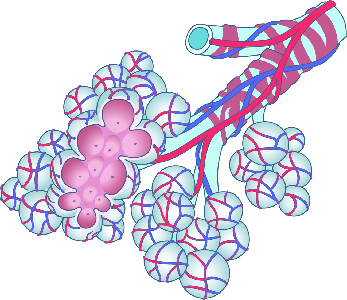

Detailreiche Fotografien aus der medizinischen Praxis ergänzen die Texte; moderne, genaue,

wissenschaftliche Zeichnungen geben Einblick in die Anatomie und die Funktion der Lunge und

anderer Organe.